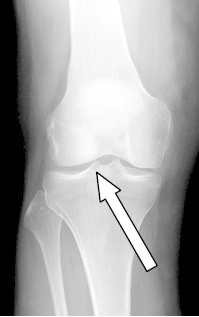

Którą strukturę anatomiczną oznaczono strzałką na radiogramie stawu kolanowego?

A. Guzek międzykłykciowy przyśrodkowy.

B. Kłykieć przyśrodkowy.

C. Kłykieć boczny.

D. Guzek międzykłykciowy boczny.